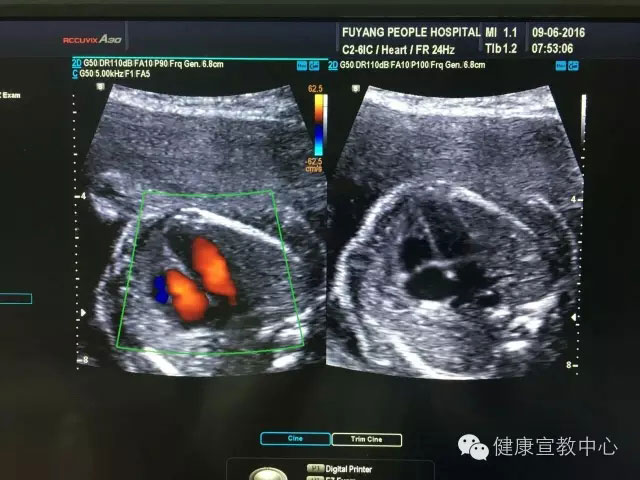

胎兒專項系統(tǒng)檢查是建立在胎兒中孕系統(tǒng)超聲檢查的基礎(chǔ)上對所篩查的器官、作更系統(tǒng)化精細(xì)化檢查。從2015年,開展胎兒專項系統(tǒng)篩查(胎兒心臟、胎兒中樞神經(jīng)系統(tǒng)、顱腦微小畸形、脊柱等)以來,共計完成400余例。目前,該項技術(shù)處于省內(nèi)領(lǐng)先水平,部分省級醫(yī)院還尚未開展。

(胎兒超聲心動圖)